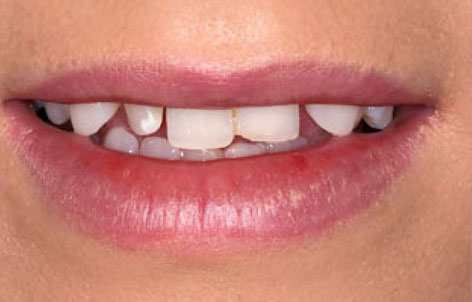

Estetik Lamina

Laminalar özellikle ön grup dişlerde uygulanabilen çok ince porselenlerdir.

Estetik Kaplamalar

Dişler üzerinde meydana gelen kırık, çatlak, çürük ve çarpma gibi etkiler sonucunda diş üzerine kaplama yapılması ihtiyacı ortaya...